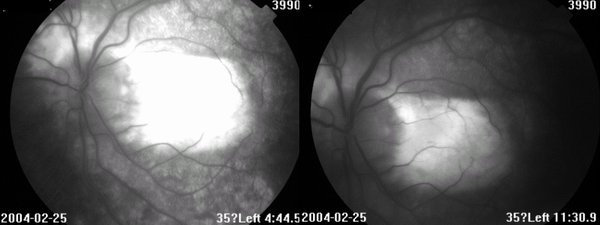

眼底见:玻璃体尘状混浊 眼底图 右眼 左眼 荧光造影图 眼科B超 OCT 视野 讨论: 1、诊断及鉴别诊断

2、眼底见病灶起自视乳头,葡行性发展,呈地图状,界清

4、FFA:早期低荧光,晚期高荧光;有荧光渗漏(CNV)、遮挡荧光(出血)

FFA:早期低荧光,晚期高荧光;如有CNV,可见荧光渗漏,或出血遮挡荧光。晚期病例:病灶边缘高荧光,中央低荧光,经常见大的脉络膜血管

ICGA:活动病灶为低荧光,脉络膜血管梗塞或渗出、水肿遮挡荧光